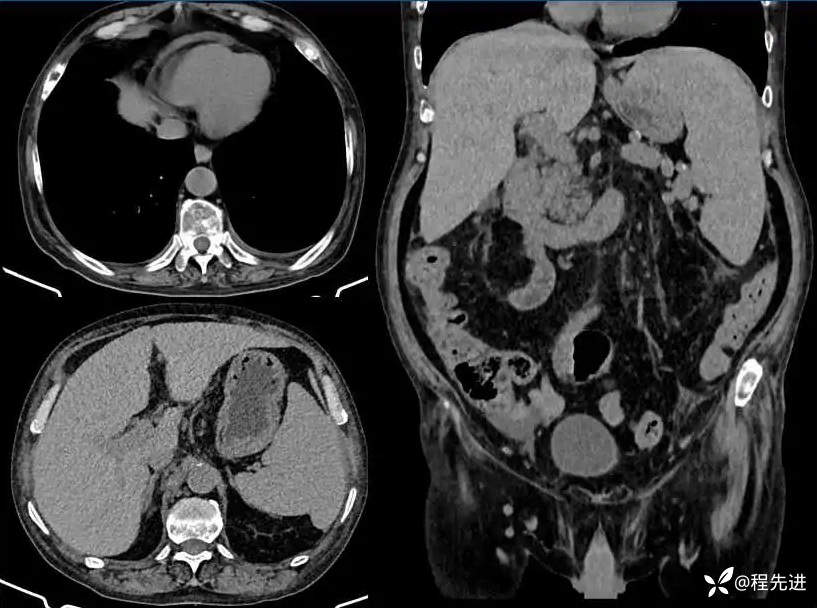

现病史:患者3月余前无明显诱因下出现双下肢水肿、麻木伴腹胀腹泻伴纳差,无恶心呕吐,无畏寒发热,无呕血黑便,无胸闷气喘。至外院内分泌科就诊:肿瘤标志物未见明显异常,便潜血(+/-)-(-)。胸腹盆腔CT平扫示:“多浆膜腔积液(心包积液、肾周渗液、盆腹腔积液)肝脾肿大;伴随多发性骨质改变。血常规提示两系减少。病程中患者自觉腹部增大,皮肤发黑,纳差,睡眠一般无寒战发热,近期体重下降5-6斤。

胸腹部: